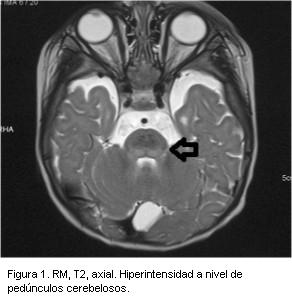

- Resonancia magnética (RM): imágenes hipointensas en T1 e hiperintensas en T2 y FLAIR, mal delimitadas bilaterales y simétricas que comprometen ambos putámenes, globos pálidos, sustancia nigra, núcleos subtalámicos, sustancia gris periacueductal, núcleos dentados y tronco encefálico, con restricción en la difusión. Cuerpo calloso adelgazado y megacisterna magna (figuras 1 y 2).

Las imágenes en la resonancia magnética que se observan de forma más característica en esta enfermedad son lesiones bilaterales y simétricas, hiperintensas en T2 en sustancia blanca periventricular a nivel parietal y occipital, correspondiendo a alteraciones en la mielinización entre otras posibles causas(12-14).

En el paciente las lesiones eran más extensas de lo habitual abarcando ganglios basales, mesencéfalo y pedúnculos cerebelosos medios. En la literatura se describe de forma excepcional dicha topografía lesional; estos hallazgos se vinculan a la elevada concentración del aminoácido en sangre. Así mismo, se describe una mayor extensión lesional en la asociación de PKU con síndrome de West, postulándose que ambas patologías participan alterando el proceso normal de mielinización(11,13).